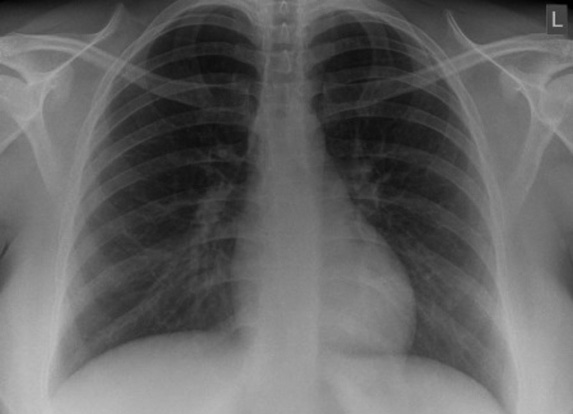

Chest radiographs findings did not indicate pulmonary tuberculosis (Figure 2). The sputum was negative (GeneXpert®; Cepheid, Sunnyvale, CA, USA). Her abdominal and thoracic ultrasound revealed massive ascites with mild septation.

Figure 2. Chest radiographs showing no pathological signs.